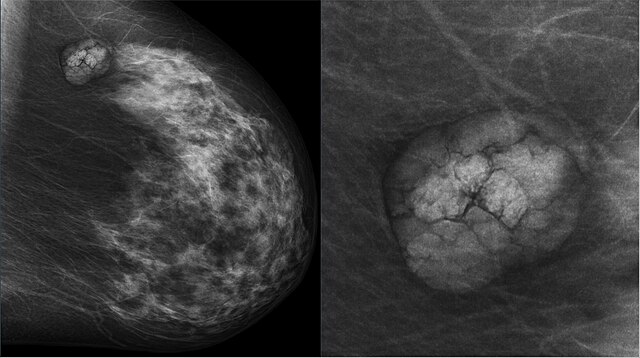

La radiologie ne se limite pas au diagnostic, elle joue également un rôle thérapeutique dans

certaines situations. En cas de saignement actif, notamment après un traumatisme ou en

présence d’une malformation artérioveineuse, une embolisation peut être réalisée. Cette

technique consiste à obturer sélectivement un vaisseau pour arrêter l’hémorragie, tout en

préservant les structures voisines.

La radiologie interventionnelle permet aussi de réaliser des biopsies ciblées sur des lésions

suspectes visualisées à l’imagerie. Guidée par échographie, scanner ou IRM, cette

procédure mini-invasive assure un prélèvement précis, essentiel pour le diagnostic

histologique.